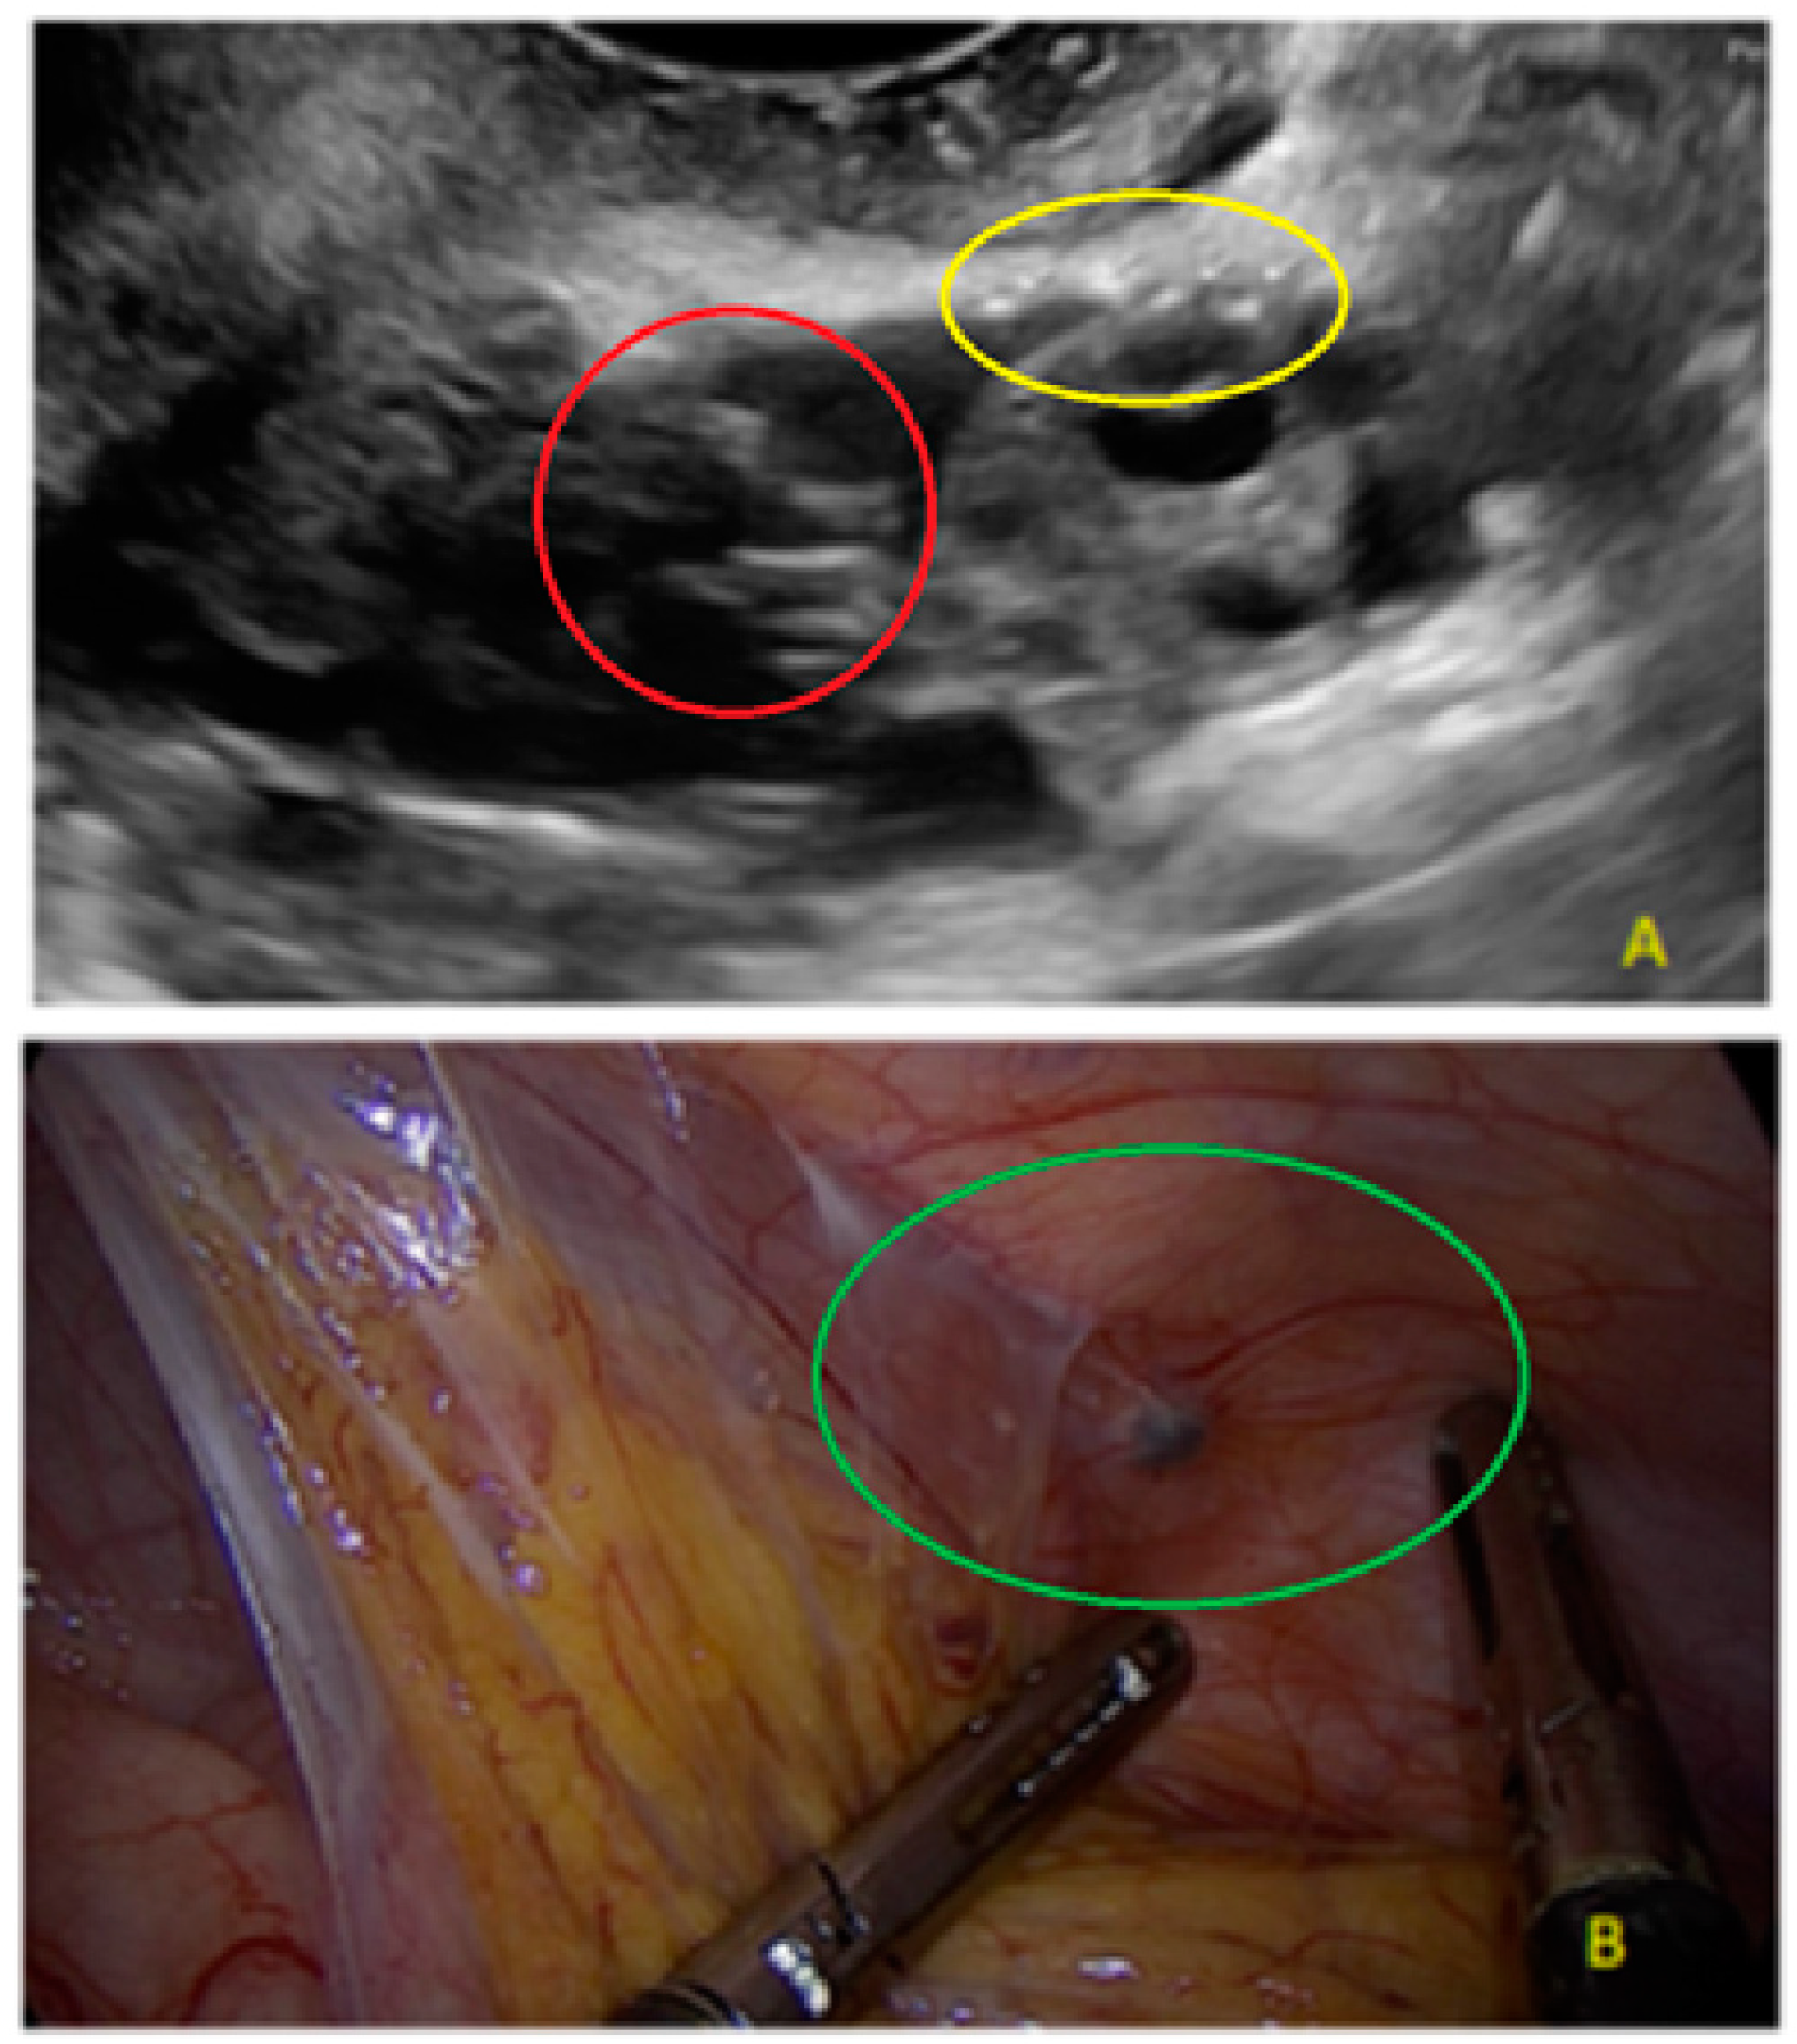

- The presence of hypoechogenic associated tissue (hypoechoic areas surrounding a small cyst area; we called this a “hat”). This tissue does not protrude or invaginate the peritoneal surface.

- The lesion may be convex, protruding from the peritoneal surface into the peritoneal cavity (we called this “bulging”), or it may appear as a concave defect in the peritoneum (we called this a “pocket”).

- The presence of velamentous (filmy) adhesions associated to the lesion (we called this a “veil”).

3.1. Cystic Solitary Lesion